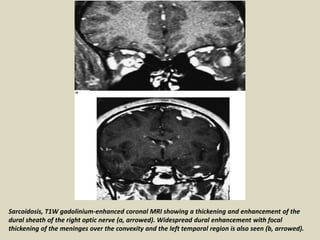

Sarcoidosis, T1W gadolinium-enhanced coronal MRI showing a thickening and enhancement of the

dural sheath of the right optic nerve (a, arrowed). Widespread dural enhancement with focal

thickening of the meninges over the convexity and the left temporal region is also seen (b, arrowed).